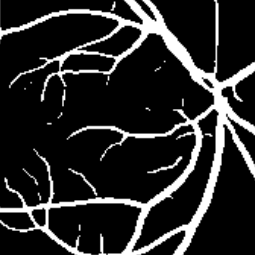

Semantic segmentation of blood vessels is an important task in medical image analysis, but its progress is often hindered by the scarcity of large annotated datasets and the poor generalization of models across different imaging modalities. A key aspect is the tendency of Convolutional Neural Networks (CNNs) to learn texture-based features, which limits their performance when applied to new domains with different visual characteristics. We hypothesize that leveraging geometric priors of vessel shapes, such as their tubular and branching nature, can lead to more robust and data-efficient models. To investigate this, we introduce VessShape, a methodology for generating large-scale 2D synthetic datasets designed to instill a shape bias in segmentation models. VessShape images contain procedurally generated tubular geometries combined with a wide variety of foreground and background textures, encouraging models to learn shape cues rather than textures. We demonstrate that a model pre-trained on VessShape images achieves strong few-shot segmentation performance on two real-world datasets from different domains, requiring only four to ten samples for fine-tuning. Furthermore, the model exhibits notable zero-shot capabilities, effectively segmenting vessels in unseen domains without any target-specific training. Our results indicate that pre-training with a strong shape bias can be an effective strategy to overcome data scarcity and improve model generalization in blood vessel segmentation.